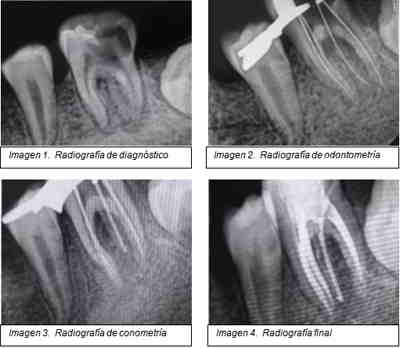

Las diferentes angulaciones de las tomas radiográficas y la morfología del órgano dentario hizo evidente el diagnostico de una tercera raíz (imágenes).

Es necesario tomar radiografías con tres angulaciones; ortoradial, mesiolingual y distolingual para identificar esta raíz adicional o algún otro método radiográfico tridimensional. Slowley (1974) demostro que tan difícil es detectar raíces extras, y más aun conductos extras. Por el contrario, completando un estudio radiográfico del diente con tres exposiciones de diferentes proyecciones horizontales, la proyección estándar bucal-lingual, 20º desde mesial, y 20º desde distal revelan una información esencial con respecto a la anatomía del diente para realizar el tratamiento endodóntico

La cavidad de acceso debe modificarse en una dirección distolingual para visualizar y tratar el Radix Entomolaris, esto produce una cavidad de acceso trapezoidal.

El objetivo principal del tratamiento del conducto radicular es la completa limpieza mecánica y química, y su completa obturación tridimensional con un material inerte y un sellado coronal que prevenga el ingreso de microorganismos.